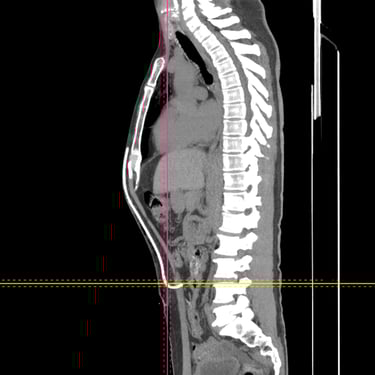

Hidrocefalia: Tratamiento mediante Derivación Ventriculoperitoneal

La hidrocefalia es una condición caracterizada por la acumulación anormal de líquido cefalorraquídeo en los ventrículos cerebrales, lo que genera aumento de la presión intracraneal y síntomas como cefalea, náuseas, alteraciones cognitivas y trastornos de la marcha. Cuando el manejo médico no es suficiente, la derivación ventriculoperitoneal (DVP) es el tratamiento quirúrgico más utilizado. Este procedimiento permite drenar el exceso de líquido desde el cerebro hacia la cavidad abdominal, donde es reabsorbido, aliviando la presión intracraneal y mejorando la función neurológica. El tratamiento oportuno es clave para prevenir secuelas.